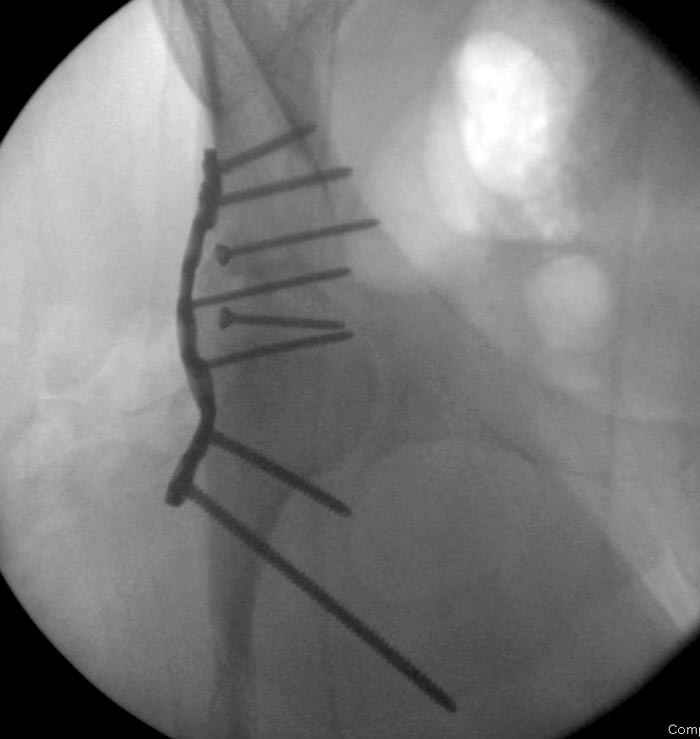

Отправитель: Alexander Chelnokov 23 Ноябрь 2004, 02:31

Если, например, доводится лечить больных с псевдартрозами шейки бедра, то надобность есть, и приходится. См. приложение.

Несколько снимков из моей коллекции, чтобы разьяснить, почему мы до сих пор делаем различные варианты остеотомии.

На рисунке N1 предоперационный план лечения ложного сустава шейки бедра- линия ложного сустава, угол и направление введения импланта, клиновидная остеотомия в градусах и миллиметрах, второй снимок после коррекции, расчет, на сколько удлиняется конечность и размеры импланта;

N3 рисунок окончательный снимок, после операции моя рентгенограмма должен выглядеть примерно как эта картина. На N4 снимке клин перед удалением; N5 послеоперации 3 нед.; N6 окончательная рентгенограмма.

(доложен в Ст. Петербурге 2003 и в Москве 2004)

варус при проксимальном отделе 95 градусной пластиной.